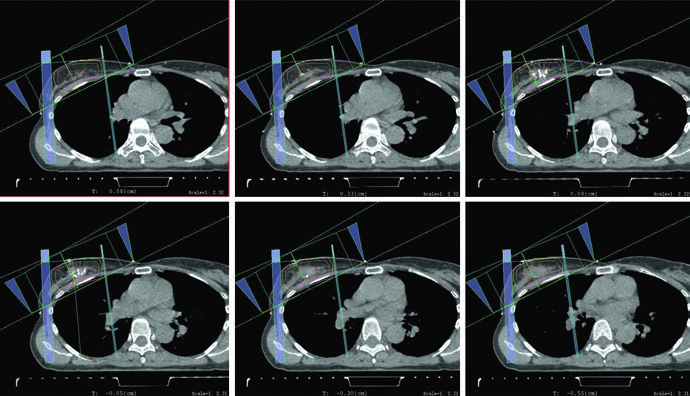

Quando o boost é indicado, o planejamento mais comum descrito pelos autores usa elétrons em incidência en face. A seleção da energia deve obedecer à profundidade do leito tumoral somada a uma margem, sem ultrapassar a superfície anterior dos músculos peitorais. A figura do boost em posição supina torna isso quase didático ao mostrar a escolha de 12 MeV para garantir cobertura da isodose de 90% até a superfície anterior do peitoral. Se o leito é profundo, o texto admite uma alternativa prática: considerar mini-tangentes.

As figuras e a tabela explicam como esse volume é construído. A cavidade de lumpectomia deve incorporar seroma, clipes e alterações marcantes do tecido glandular. A tabela recomenda expansão de 1,0 a 1,5 cm para o CTV e de 0,5 a 1,0 cm para o PTV, conforme incerteza de setup e movimento previsto. Já a legenda da figura de APBI mostra um exemplo típico: CTV de 1,5 cm ao redor da cavidade, excluindo músculo peitoral, costela e parede torácica, sem ultrapassar o tecido mamário contornado e sem chegar à pele, ficando restrito a 5 mm da superfície. Em seguida, o PTV é formado por expansão de aproximadamente 5 mm em torno do CTV, dependendo da incerteza institucional.

Essa combinação entre tabela e figura afasta dois erros comuns. O primeiro é expandir o volume de forma automática, sem checar onde o tecido mamário realmente termina. O segundo é transformar o PTV em um volume anatomicamente limpo demais, esquecendo que o próprio capítulo permite que ele ultrapasse a superfície e avance para peitoral ou parede torácica quando isso decorre da margem de setup. Em APBI, o texto pede duas coisas ao mesmo tempo: disciplina anatômica no CTV e honestidade geométrica no PTV.

A figura do plano de APBI fecha esse bloco de forma coerente com o restante do capítulo. O arranjo usa mini-tangentes fotônicos combinados com um campo de elétrons en face. Não há nenhuma tentativa de tratar APBI como algo descolado do raciocínio da mama inteira. O que muda é o volume abordado, mas o capítulo continua exigindo o mesmo cuidado com orientação dos campos, profundidade útil do boost e correspondência entre anatomia operada e distribuição de dose.

As figuras do capítulo não servem apenas para ilustrar o texto; elas refinam a tomada de decisão. As imagens axiais em supino e prono mostram como a relação entre mama, pulmão e coração muda com o setup, e isso explica por que o capítulo não trata a posição da paciente como questão de preferência pessoal. A figura de APBI, por sua vez, aproxima a regra abstrata da expansão do que realmente se vê na tomografia, deixando claro onde o CTV deve parar e onde o PTV pode ultrapassar a superfície.